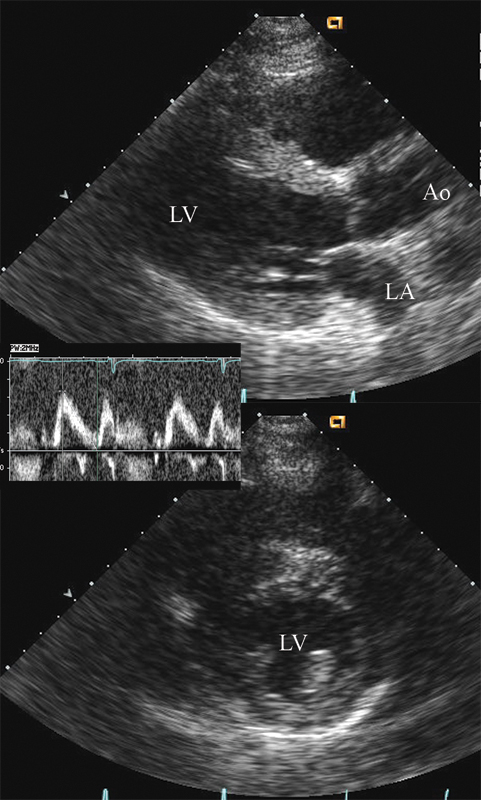

فحوصات تشخيصية لبعض امراض القلب والشرايين التاجية